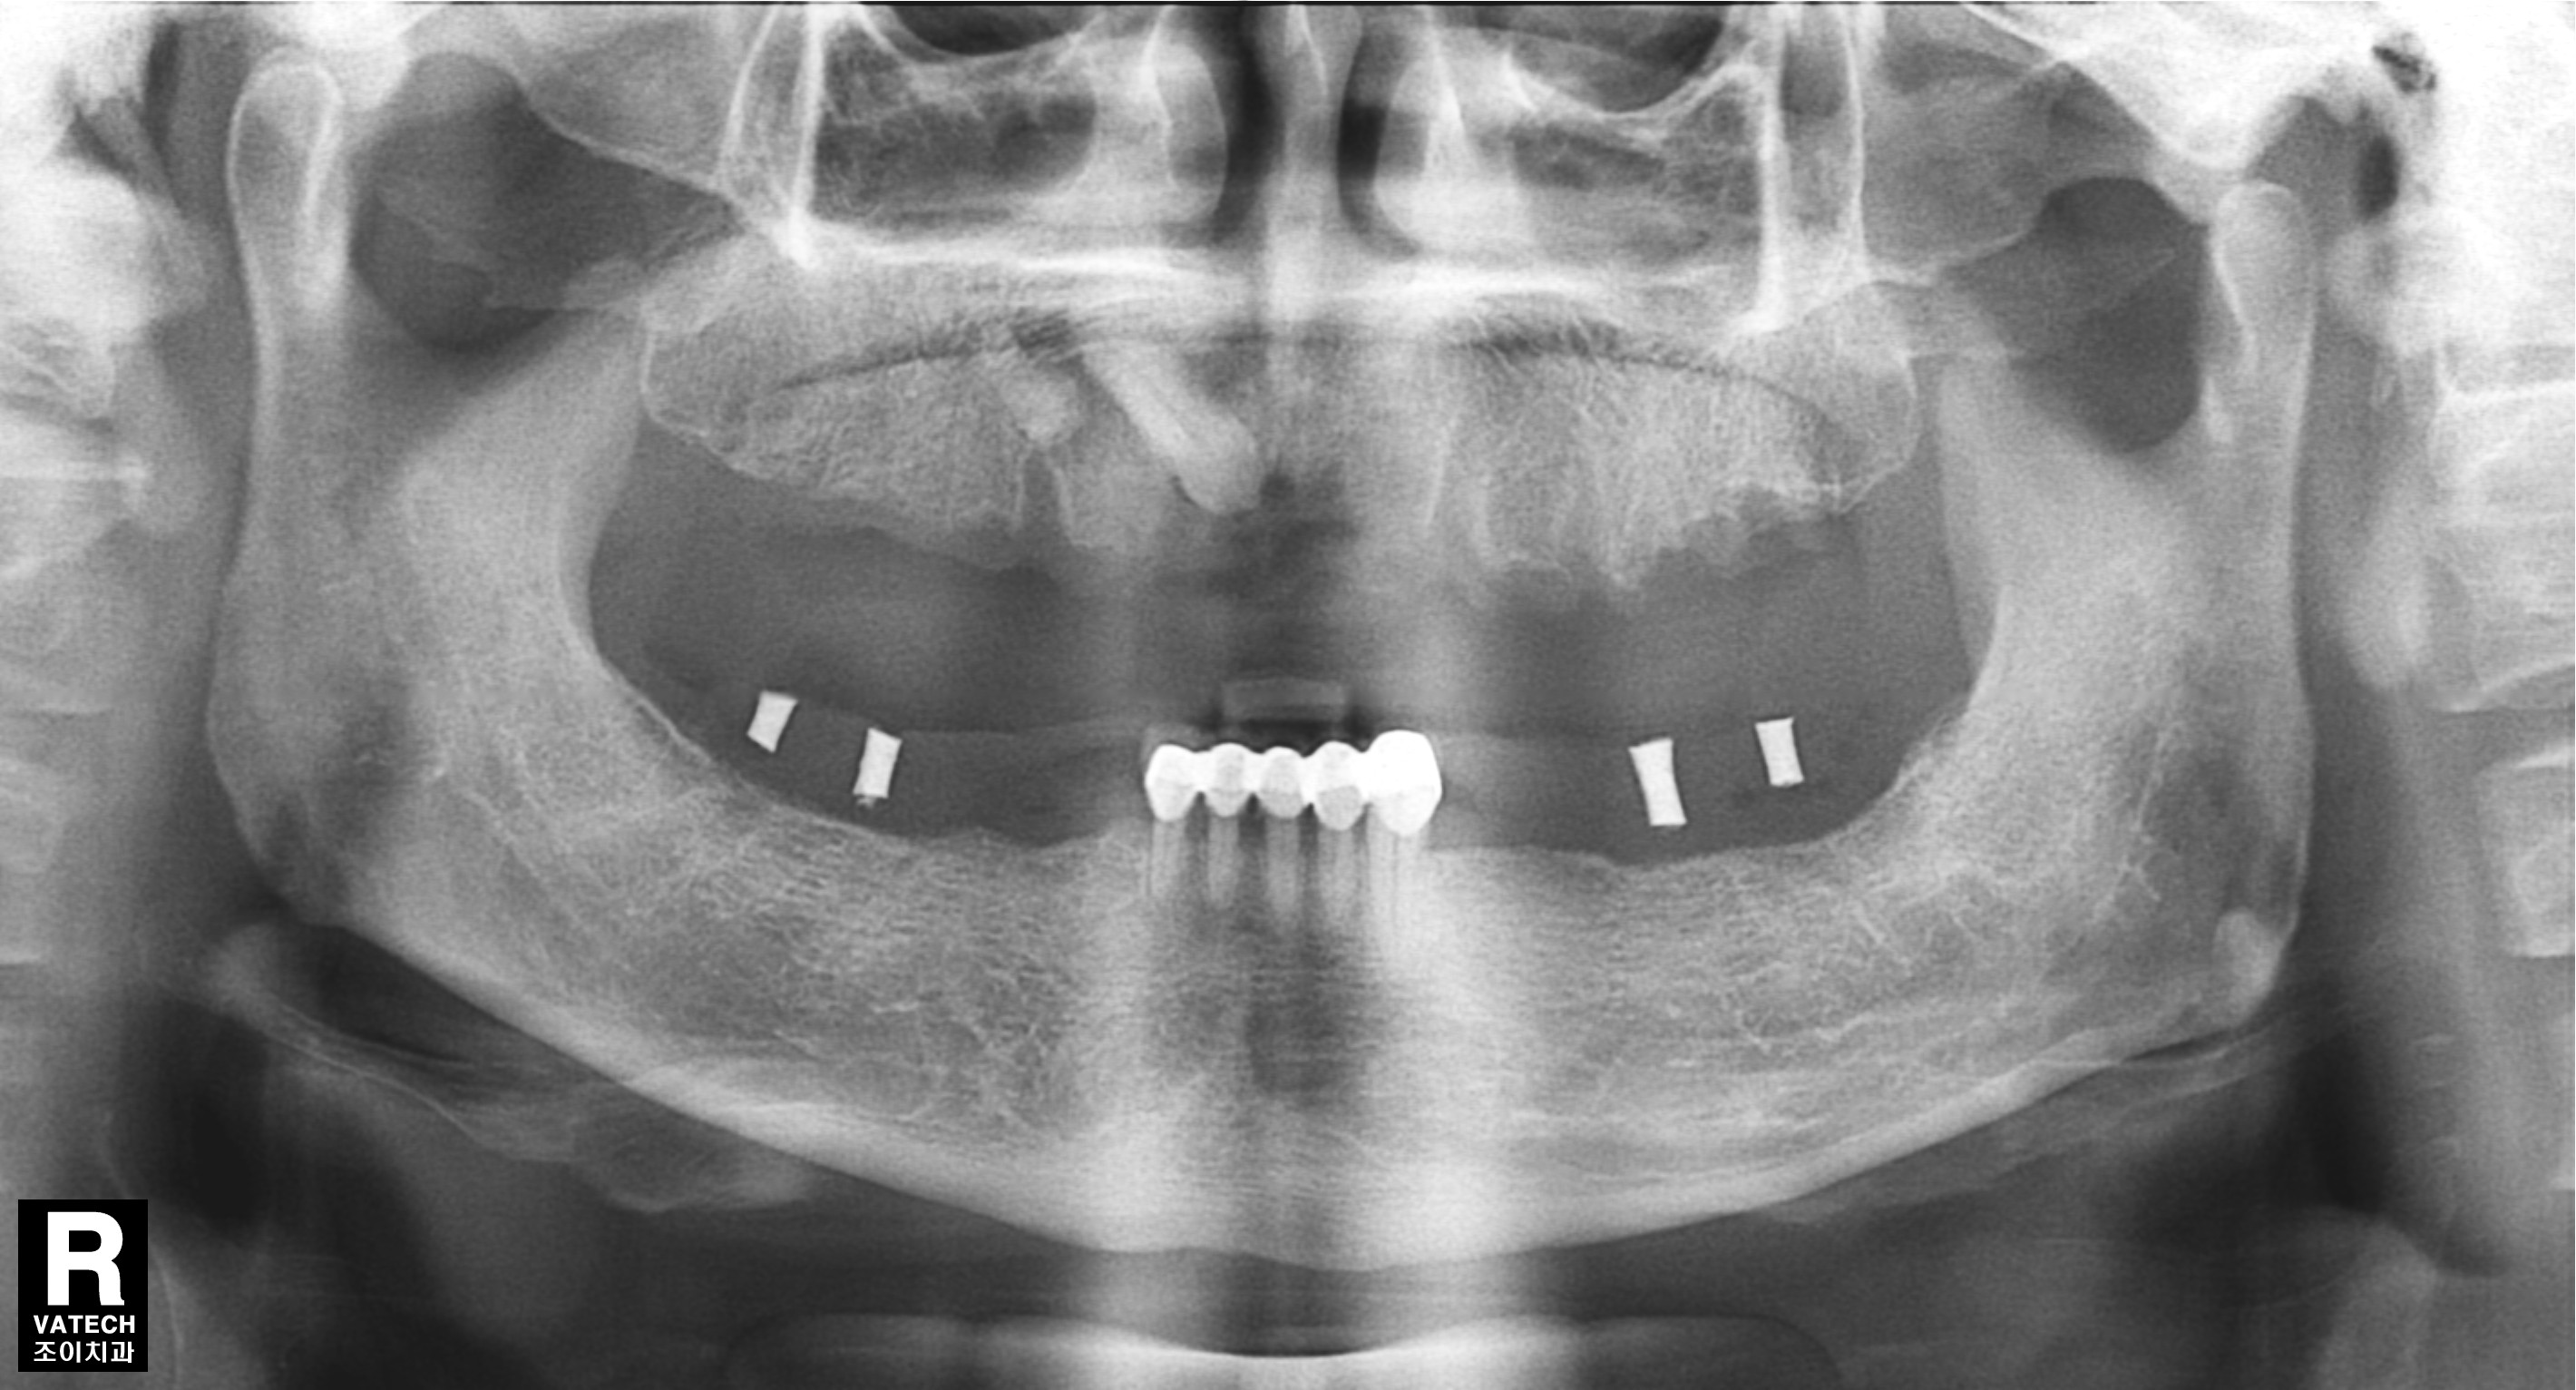

[임플란트] 제목 : 임플란트 지지 틀니

소수의 임플란트로 틀니사용을 편하게. .